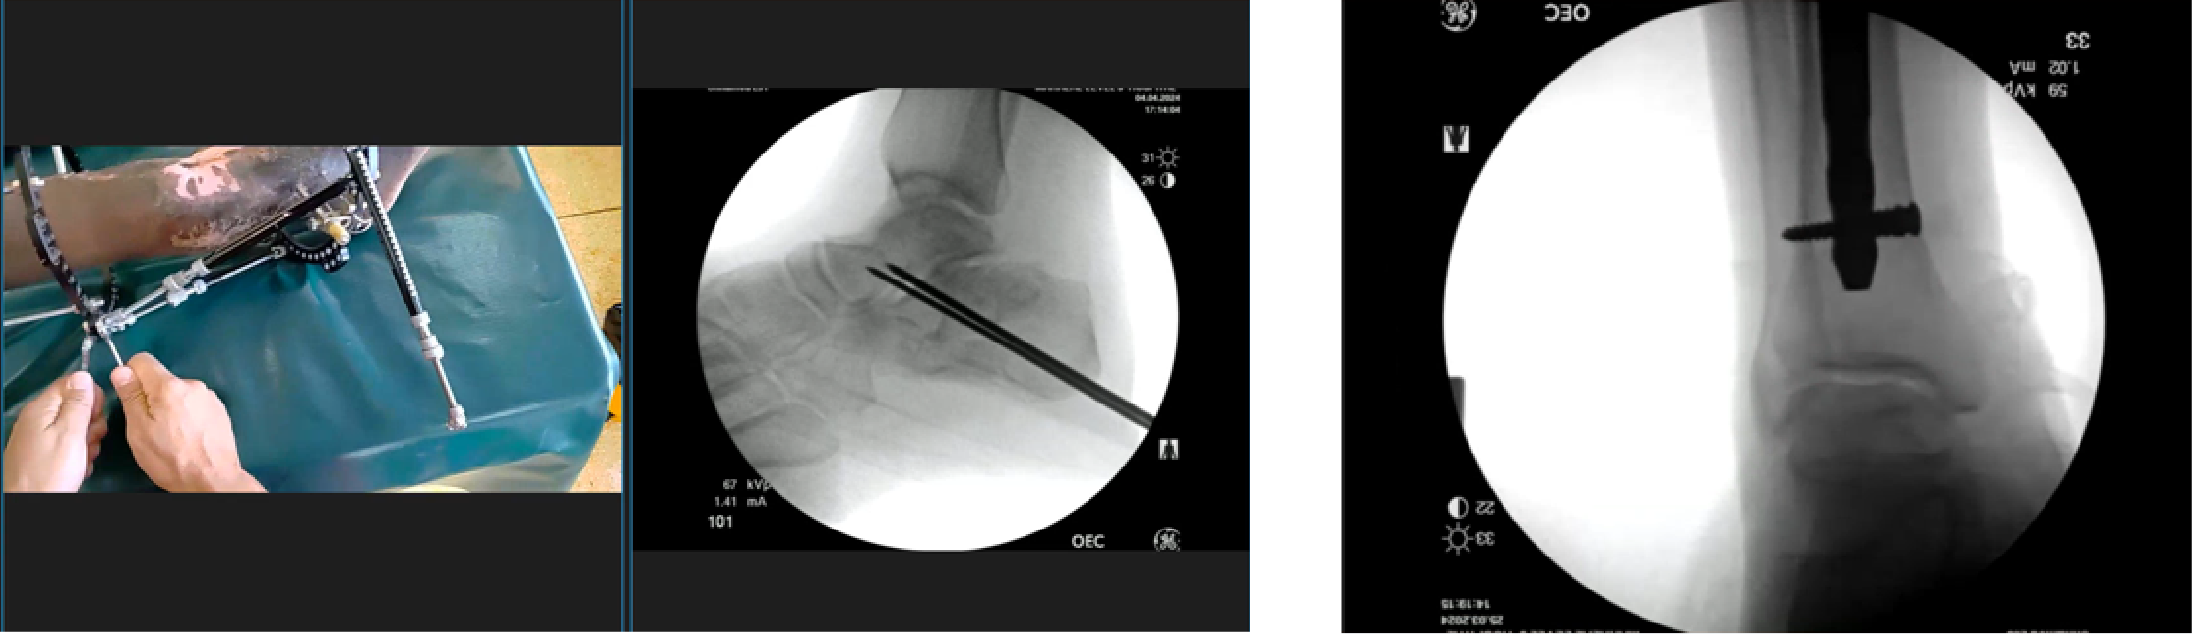

The view on the right shows the preparation of the docking site, with Dr. Scuito wearing M400 Smart Glasses. Through this technology, the mentor can view the procedure remotely, providing real-time guidance and feedback.

The view on the left shows the remote mentor’s perspective of Dr. Scuito's patient and x-ray. The patient is undergoing treatment for a calcaneal fracture that is in the process of being repaired.

Finally, on the right, a control of an interlocking tibia nail is highlighted. The remote mentor, Dr. Luigi Spreafico, is overseeing this aspect of the procedure from a distance, offering expertise and support as Dr. Scuito performs the work on-site.